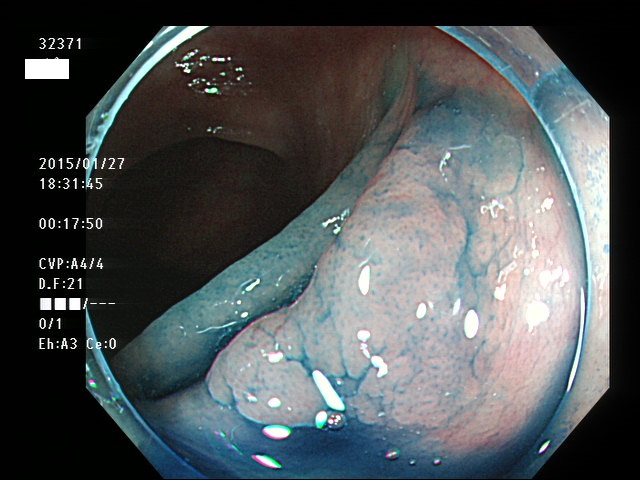

上記100名より抽出した平坦・陥凹型腺腫(=癌化の危険が高いが見落としやすい病変)の内視鏡写真

32354 32357 32359 32362 32363 32364 32365 32366(SSA/Pのみ) 32368 32369 32370 32371 32372 32373 32374 32375 32376 32378 32379 32380(SSA/Pのみ) 32381 32382 32383 32384 32385 32386 32388 32389(SSA/Pのみ) 32390 32391(SSA/Pのみ) 32392 32395 32396 32397 32398